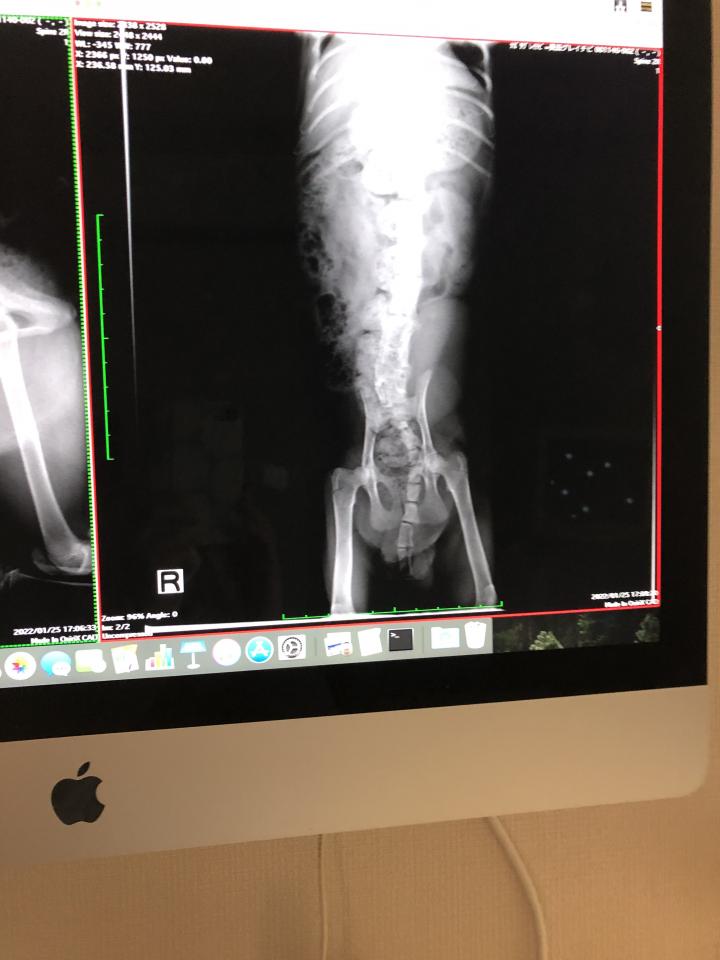

昨日ちぃちゃんの下半身の精密検査のお話&定期検診に行ってきました。

精密検査前のレントゲンも撮りました。

567がくっついてしまっているということで、やはりCT.MRIが必要のようです💦